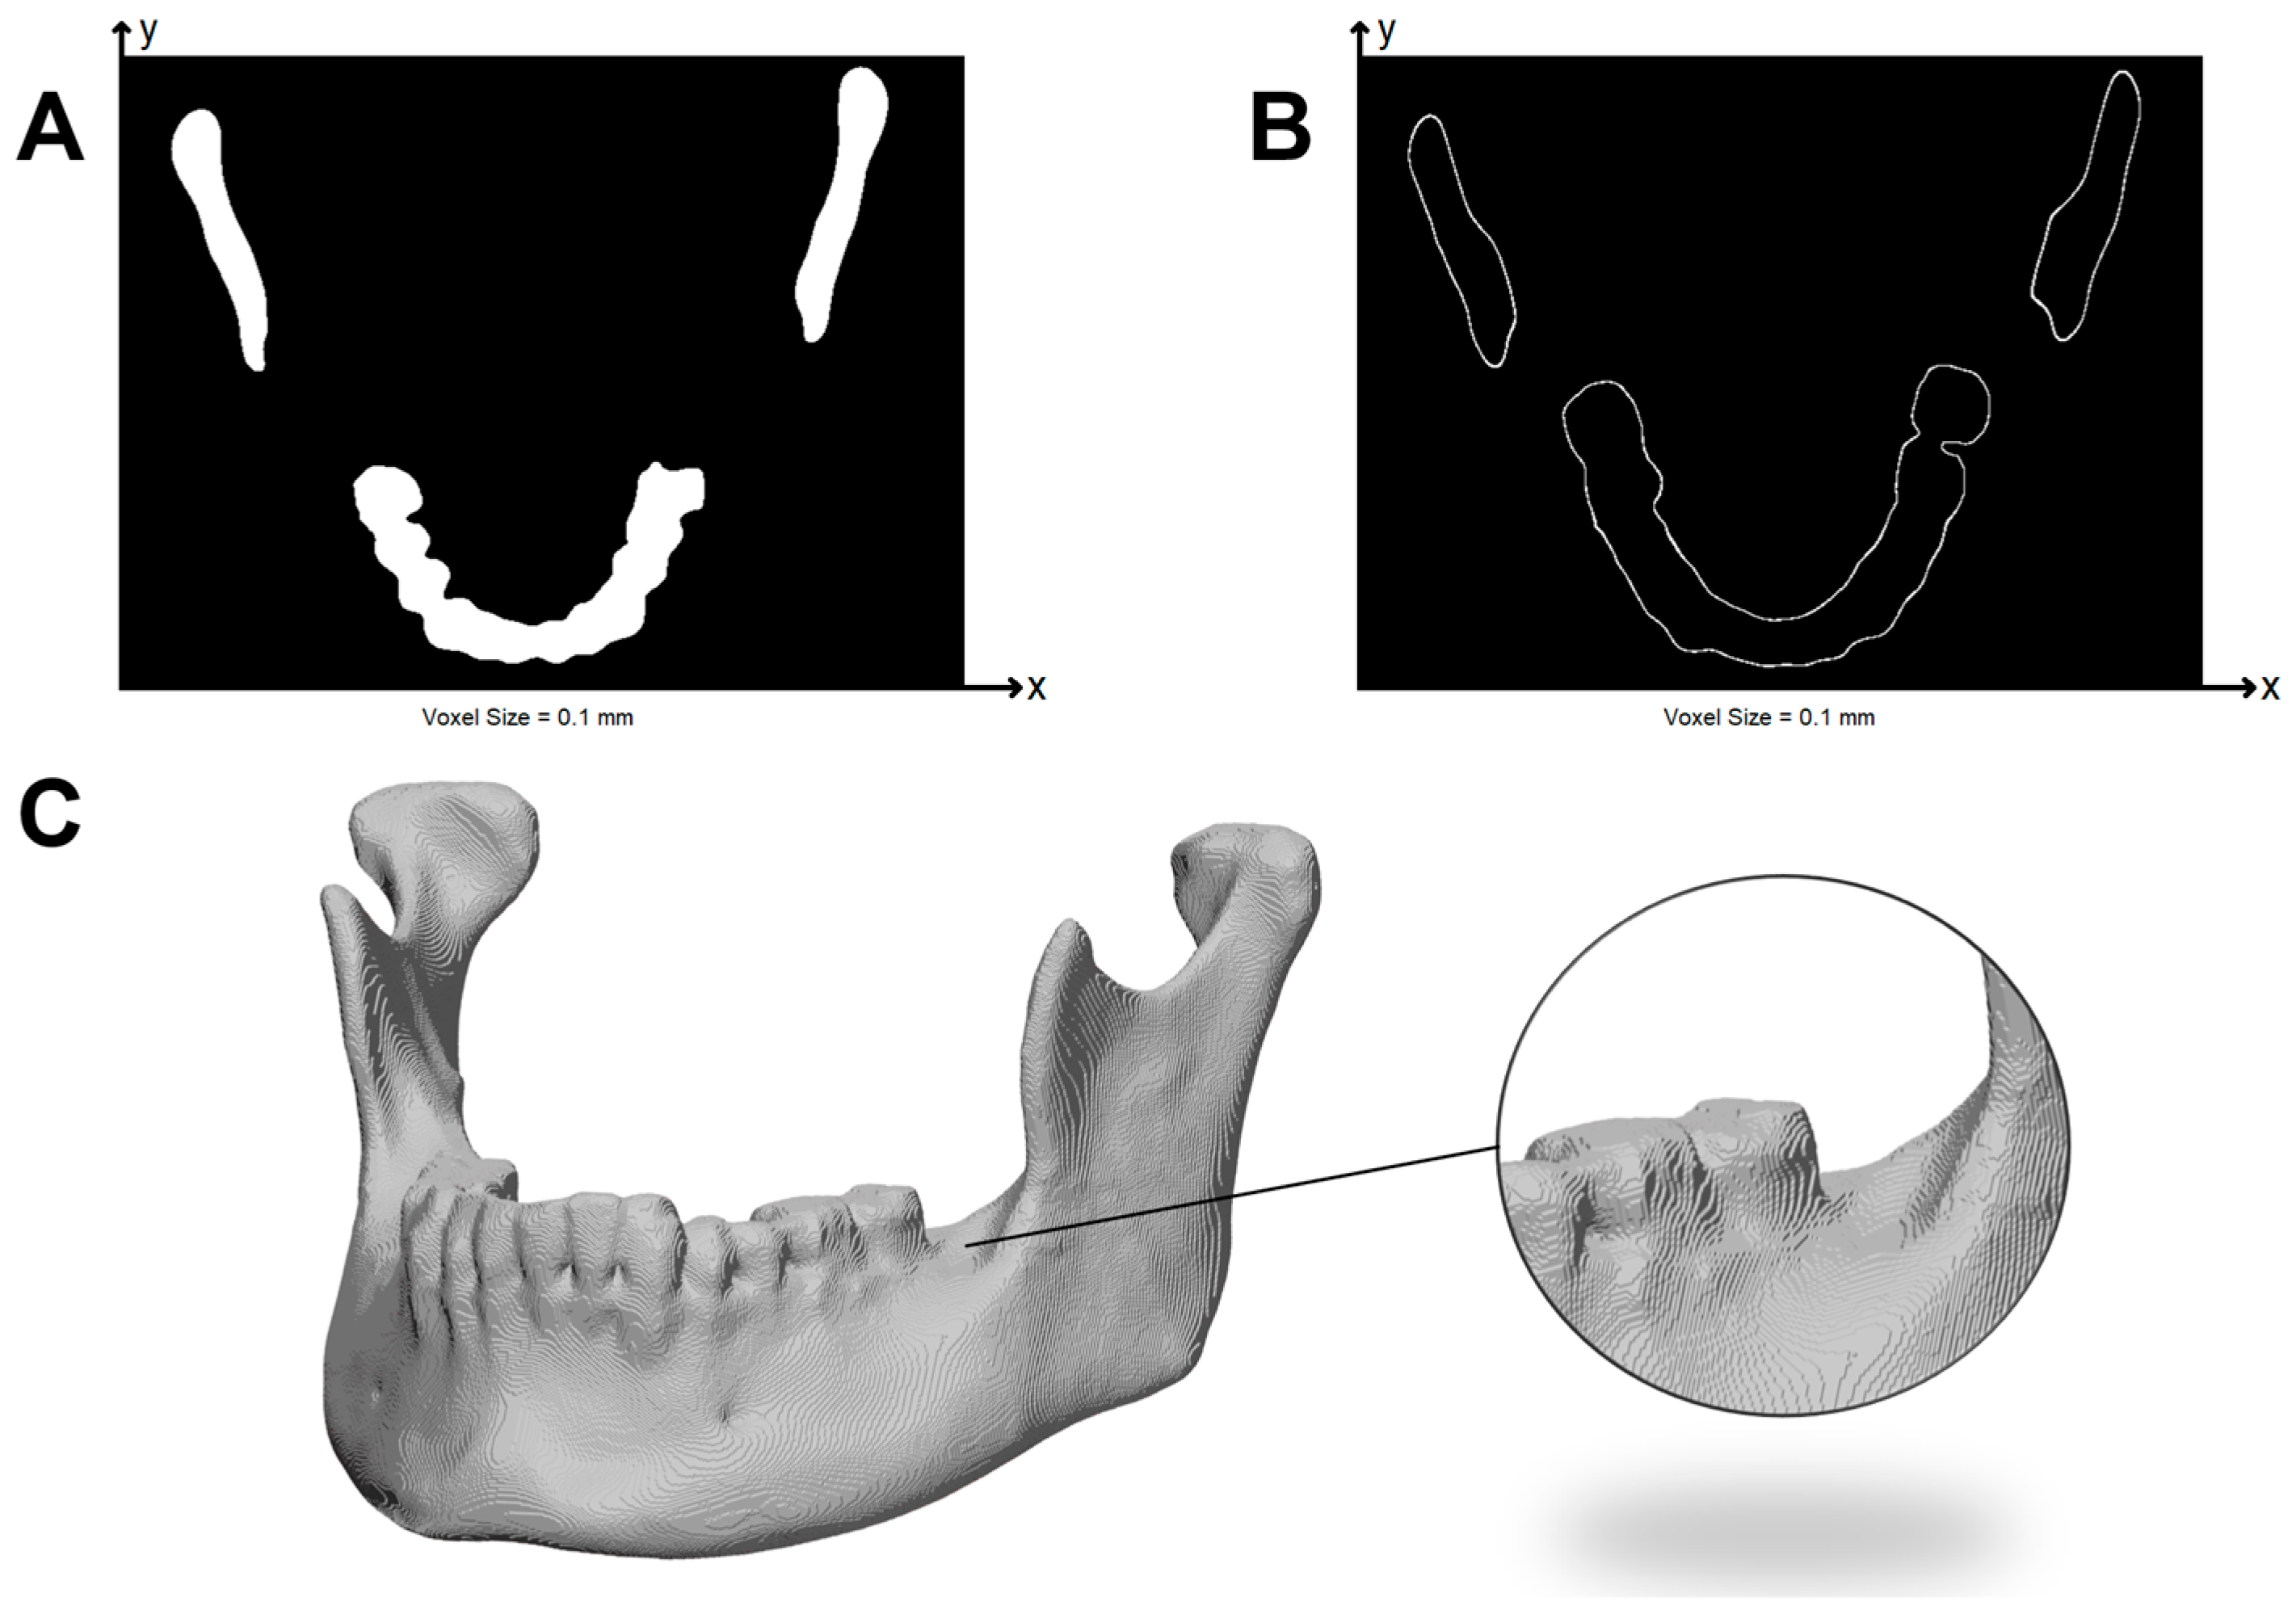

2.6. G-Code to STL

In order to perform a volumetric comparison, the previously calculated point cloud (PC4) was transformed into an STL object. Because all slicers were configured with a fixed layer height of 0.20 mm, the slicer-derived value extracted from each G-code file was identical. The volumetric reconstruction therefore used this same 0.20 mm height for all layers, ensuring consistency across slicers. The resulting volumes were merged sequentially to reproduce the layer-by-layer deposition process. Within each individual layer, all points were identified and a 2D surface was generated by connecting each point with its previous and following points defined in the G-code. This generated surface was then extruded by the slicer-defined layer height of 0.2 mm in +Z direction, simulating the nominal deposition step. This process was repeated for every layer and the resulting extruded volumes were combined into a single mesh. The volumetric reconstruction is displayed in Figure 6.

Figure 6. Volumetric reconstruction of a mandible from G-code data, generated by layer-wise extrusion of the toolpath-derived surface. The inset highlights the characteristic step-wise layering produced by the 3D printing process, accurately captured during STL conversion.